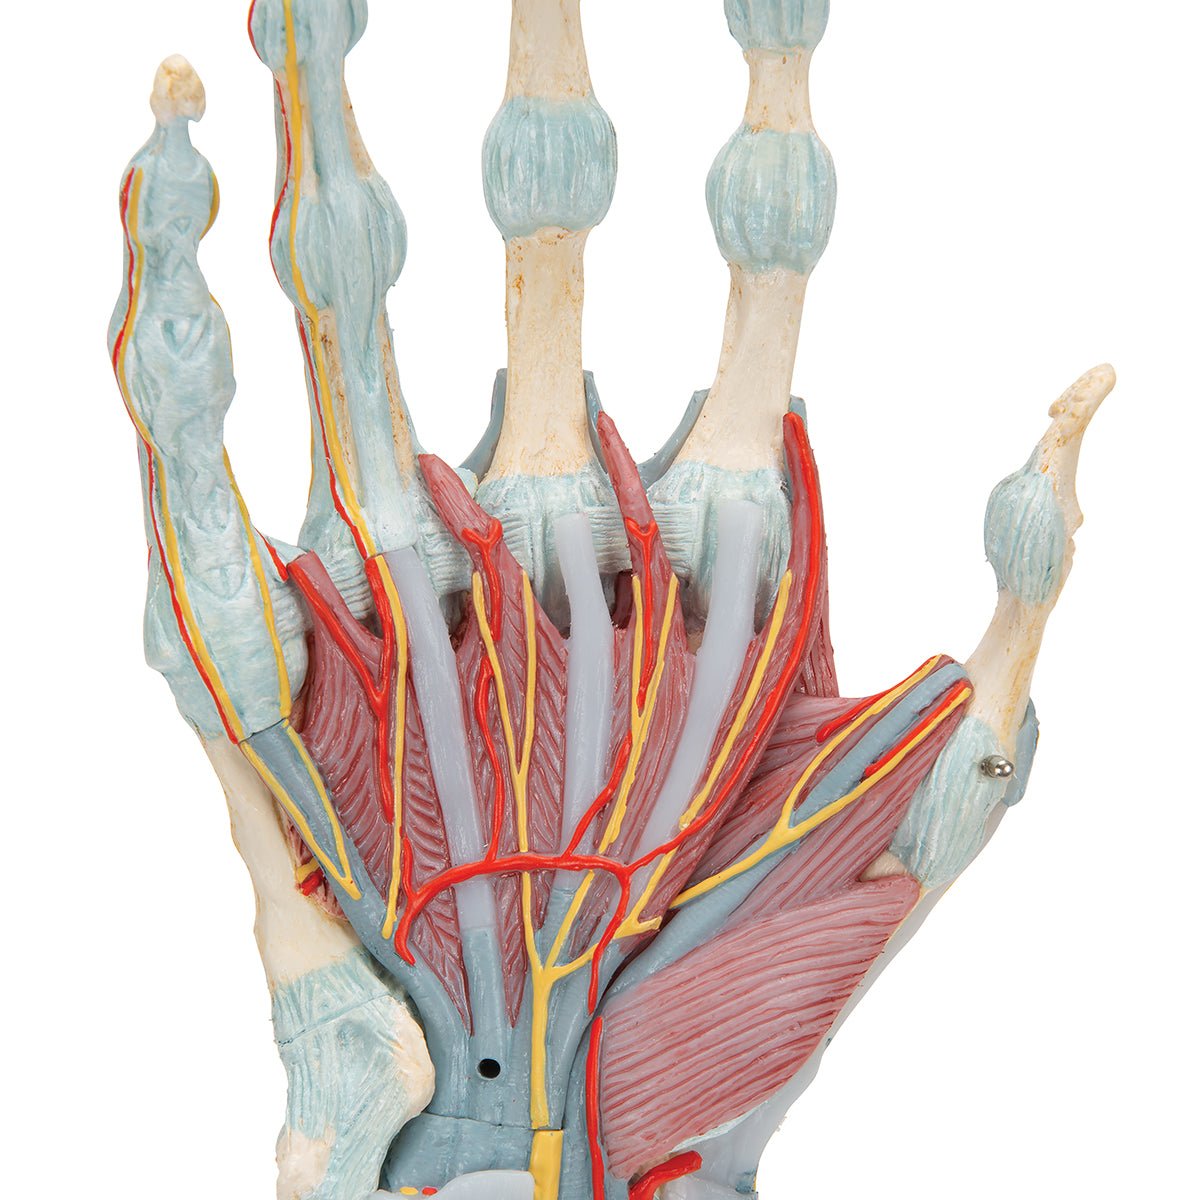

Salg af anatomiske modeller er det bærende element i eAnatomi, selvom vi også bruger mange ressourcer på at udvikle vores egne anatomiske materialer som fx plakater. Anatomiske modeller anvendes til forskellige formål og kan både vise afgrænset væv, organer samt organsystemer. Søger du en simpel model af knoglevæv eller måske en avanceret torso-model baseret på MRI teknologi, kan du finde det hele på eanatomi.com.